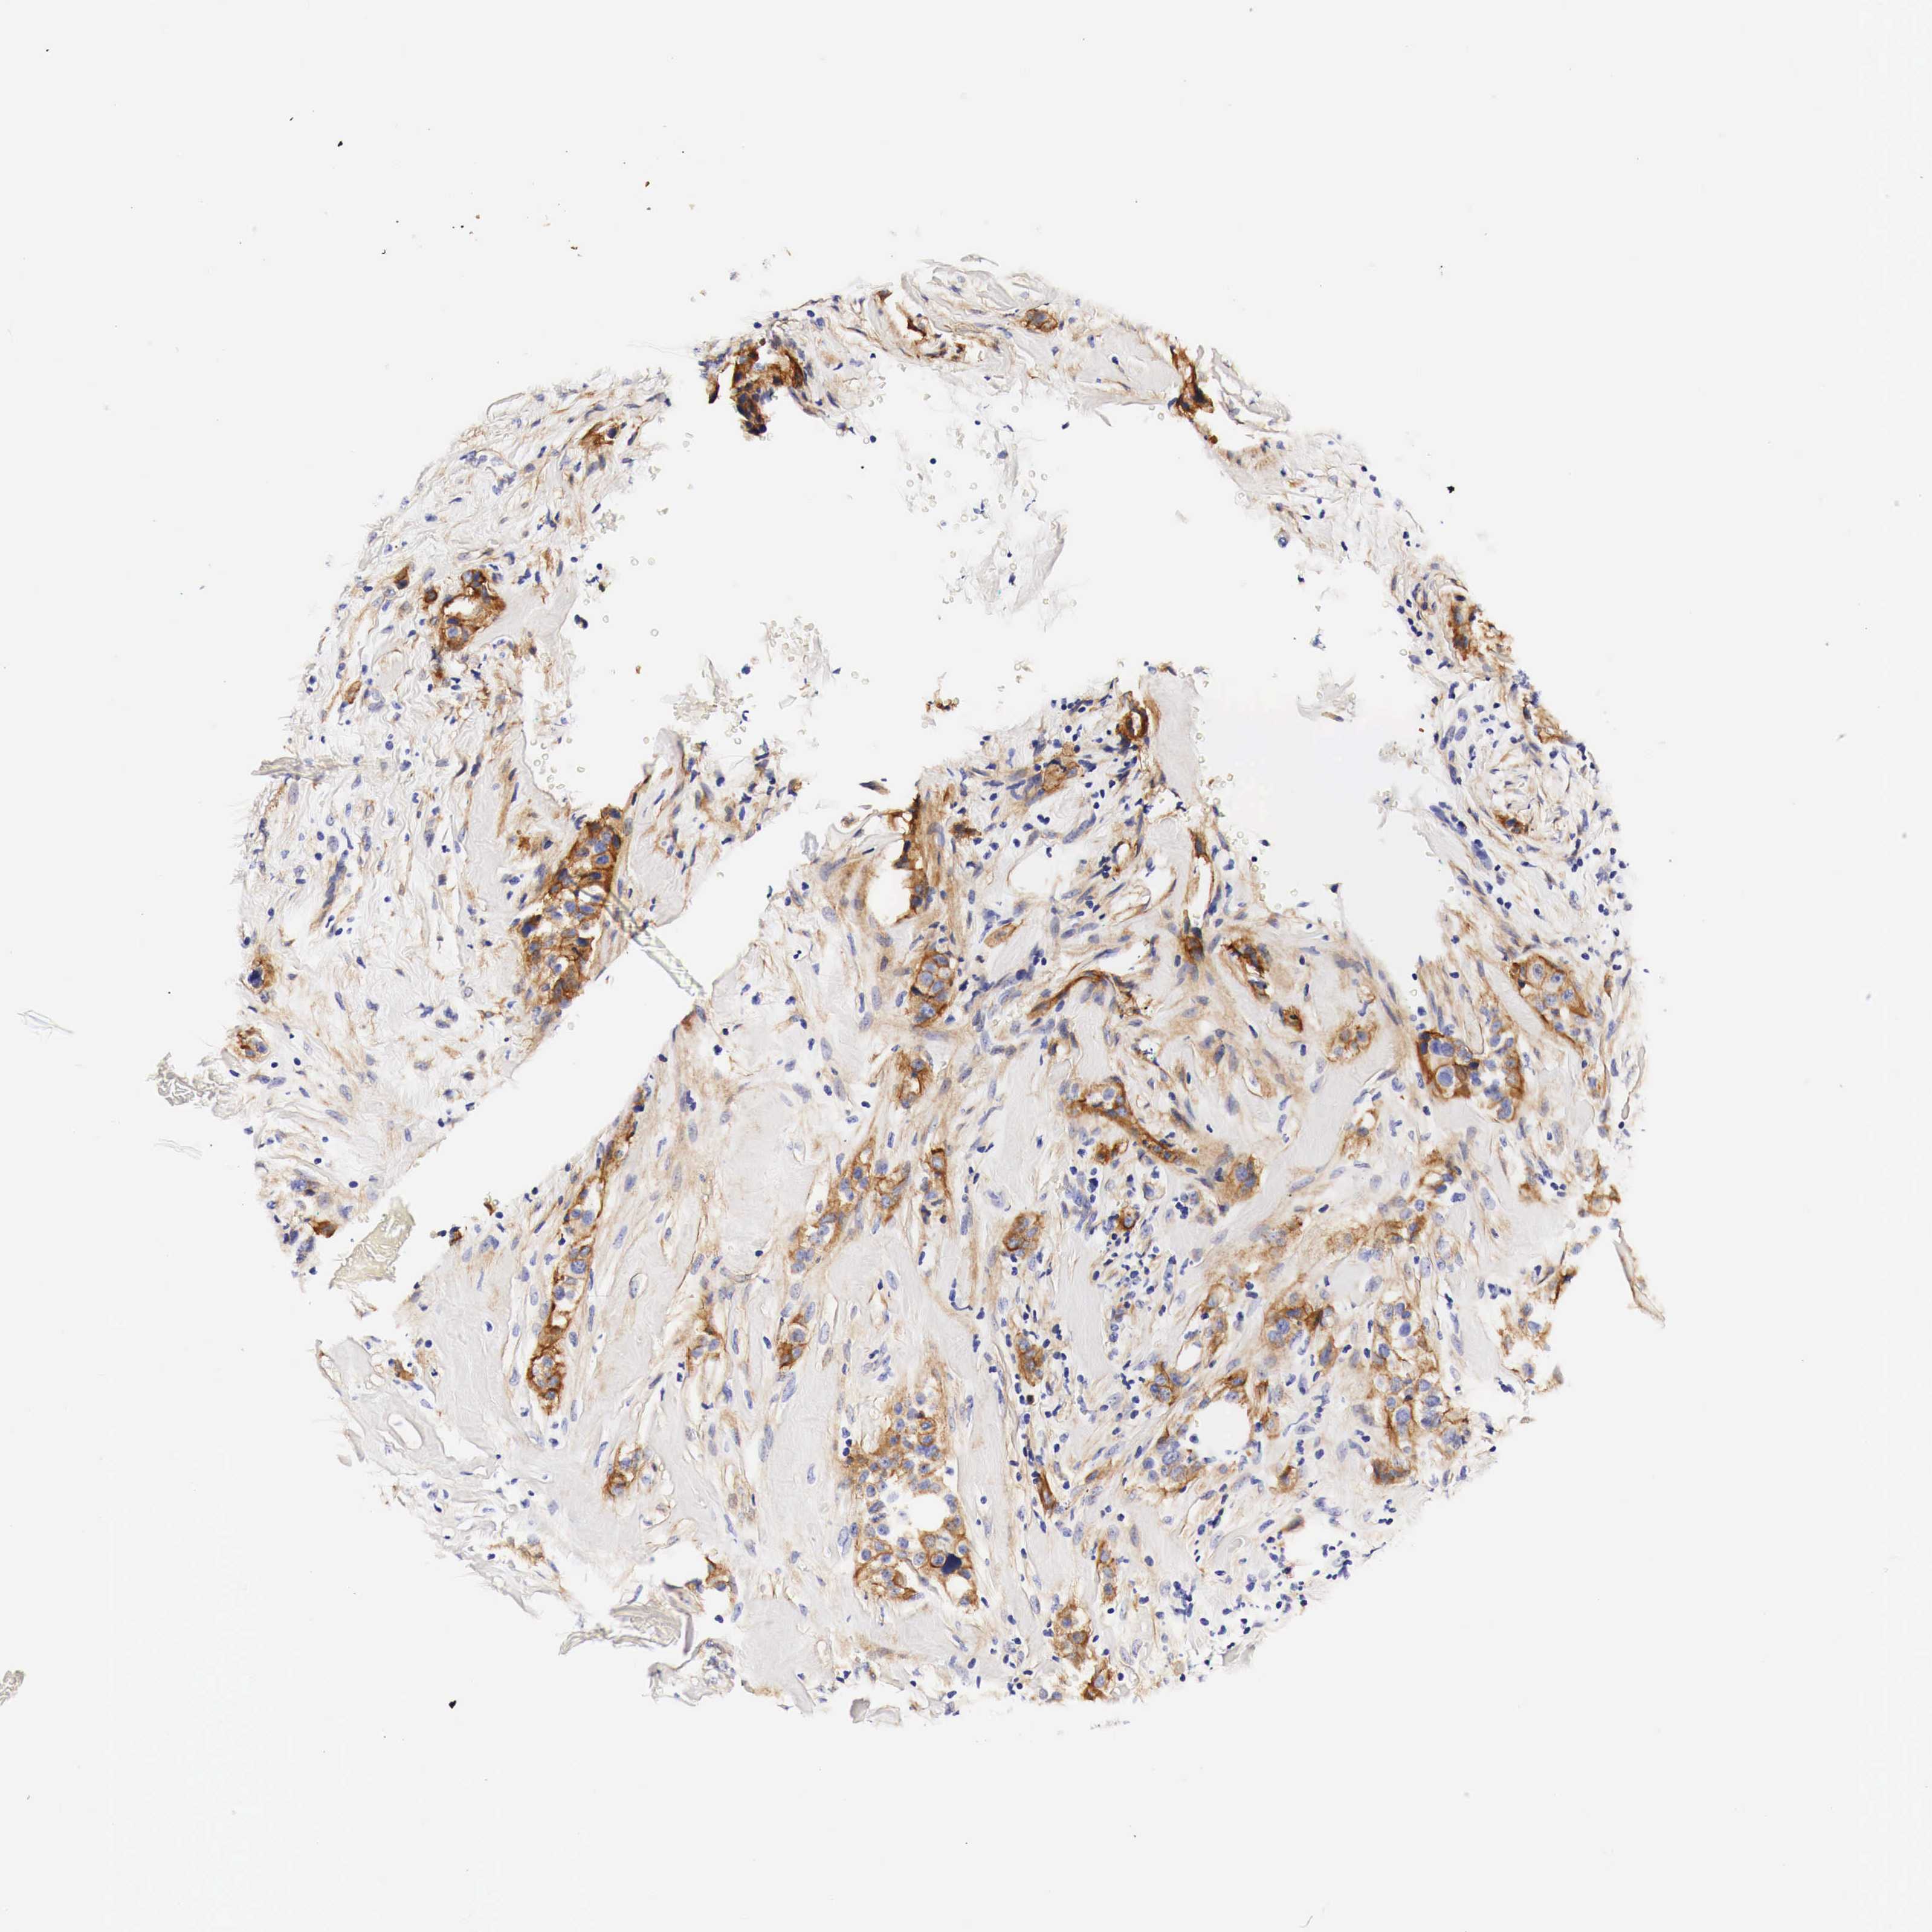

CANCER BREAST CANCER Show tissue menu

BRCA TCGA BRCA VALIDATION PROTEIN EXPRESSION

ANTIBODIES

AND

VALIDATION